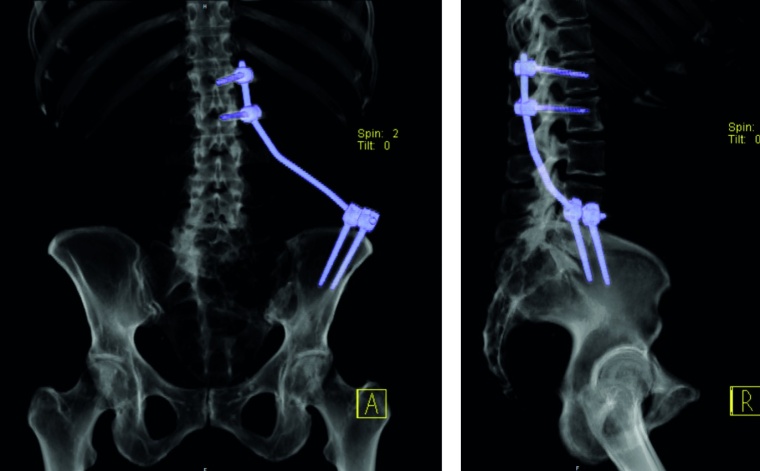

Sakrummetastasen: Stabilitätsgefährdende Metastasen am Sakrum (Abb. 3a) und am hinteren Beckenring werden zumeist mit einer mono- oder bilateralen vertebropelvinen Abstützung versorgt (Abb. 3b). Insbesondere das Os sacrum kann so aus der lasttragenden Kette herausgenommen werden. Vor allem bei Mammakarzinommetastasen kann mit der nachfolgenden Radiatio häufig eine so stabile Rekalzifikation erzielt werden (Abb. 3c), dass mitunter bei Beschwerden über dem Fixateur besonders bei schlanken Patienten eine Metallentfernung erwogen werden kann. Sollte das dorsale Os ileum mit betroffen sein (Abb. 4a) kann bei entsprechenden anatomischen Voraussetzung (Abb. 4b) auch weiter ventral auf den Beckenkamm abgestützt werden (Abb. 4c).